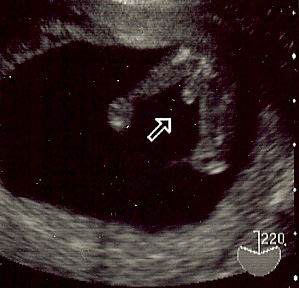

妊娠14週6日のエコーです 突起が見えますが 男の子でしょうか Yahoo 知恵袋

こんにちは 現在妊娠中で 14週のときのエコー画像なのですが お股の間 Yahoo 知恵袋